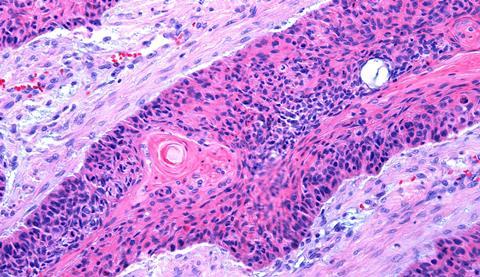

A topical cream that activates the skin’s immune defences has been shown to suppress tumour growth in early models of cutaneous squamous cell carcinoma.

Cutaneous squamous cell carcinoma is among the most frequently diagnosed cancers. Around one million Americans are diagnosed with the disease every year and its incidence continues to rise as populations age and sun exposure increases.

In most cases the cancer can be successfully treated with surgery. However, up to five percent of tumours spread beyond the original site, leading to thousands of deaths each year in the United States.